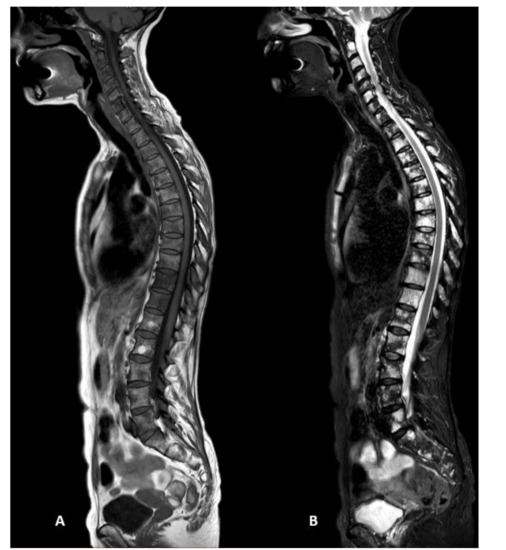

3.4. Standard vs. Short Protocols

3.5. Acquisition Time